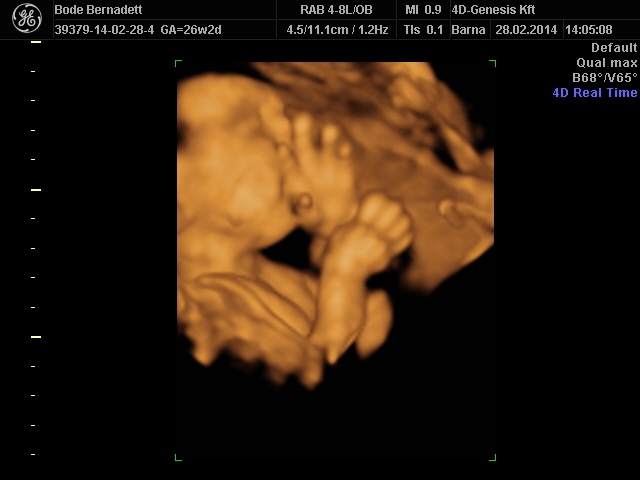

És már biztosan nagyon szépek lesznek a képek, alig várom, hogy feltöltsd, és láthassam. ![]()